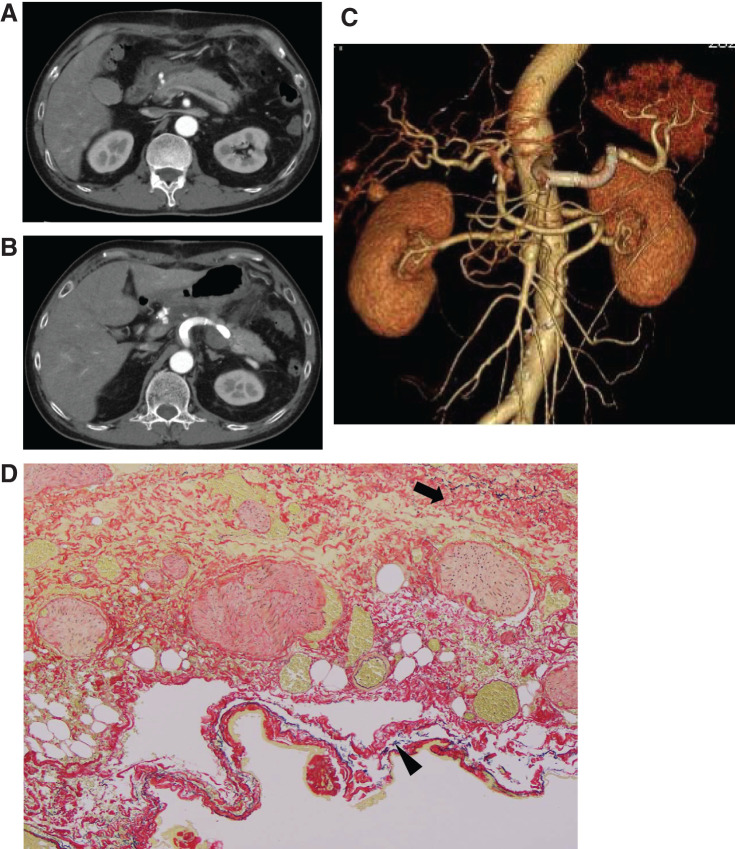

A 59-year-old patient was undergoing careful monitoring of an isolated superior mesenteric artery dissection discovered 6 years prior. He was admitted after outpatient imaging revealed multiple visceral aneurysms including common hepatic and splenic artery aneurysms that had enlarged. Based on anatomical reasons and the past history, the splenic artery aneurysm was treated with endovascular therapy, while the common hepatic artery aneurysm was resected, and blood flow reconstruction was performed. The patient was discharged without any complications. Visceral artery aneurysms have diverse locations and morphologies, illustrating the importance of treatment strategies that consider the blood flow to the organs.